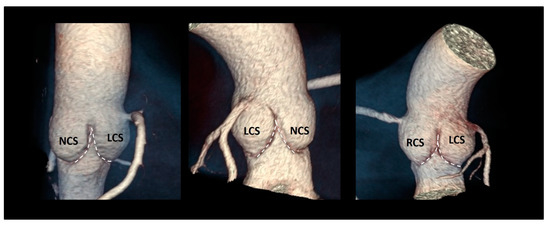

| Ventricular–arterial junction | The term ventricular–arterial junction describes the border between the ventricular myocardium and the fibroelastic structure of the aortic root. Contrary to the right AV junction, where the pulmonary root is entirely supported by the muscular infundibulum, only the left and the right coronary sinuses are partially supported by the myocardium (see text), being the remaining extent of the aortic root supported by fibrous tissue (MS = membranous septum; see text and references [12,13]). | ![]() |